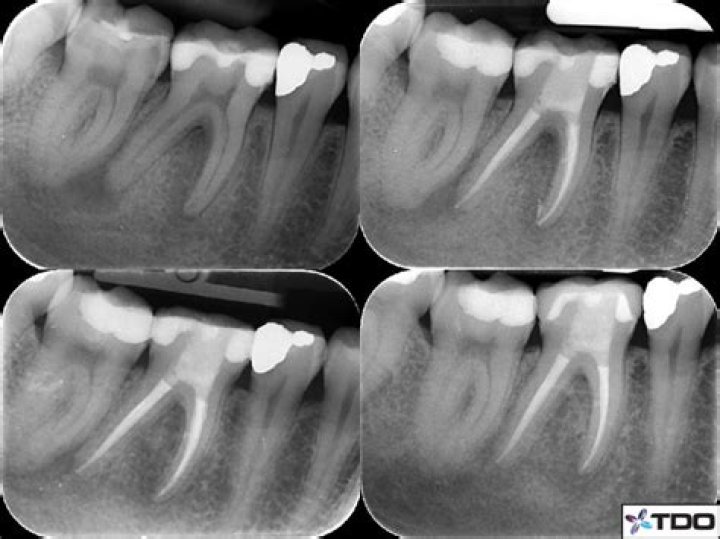

Large PARL Healing after Orthograde Endodontic Treatment Australian

What is a periapical radiolucency? Perio Implant Advisory